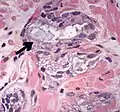

Intraductal adenocarcinoma 2.8%[10]

H&E and CK5/6

• Carcinoma cells spanning entire lumen of ducts and acini[11]

• At least focal preservation of the basal cell layer[11]